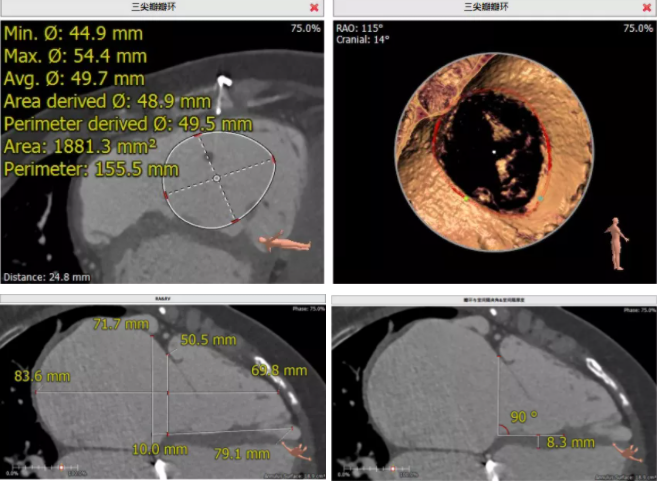

患者64歲女性,18年前接受了“正中開胸二尖瓣機(jī)械瓣置換術(shù)”,2年前超聲檢查發(fā)現(xiàn)“三尖瓣重度返流”。輾轉(zhuǎn)多地,嘗試各種治療方式,均無明顯改善。由于存在相關(guān)合并癥,傳統(tǒng)外科手術(shù)風(fēng)險(xiǎn)大,郭惠明教授團(tuán)隊(duì)結(jié)合該患者CT、超聲檢查結(jié)果,對該患者的情況進(jìn)行了充分的評估和討論,決定采用LuX-Valve人工三尖瓣介入瓣膜置換系統(tǒng)對患者進(jìn)行微創(chuàng)介入治療,以最小的創(chuàng)傷解決患者的病痛。

術(shù)前CT評估